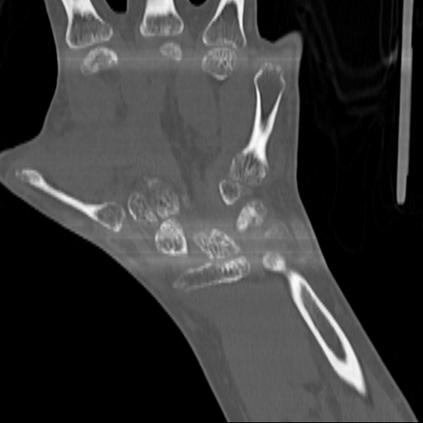

CT reconstruction provides radiologists with images for diagnosis and treatment, yet current deep learning methods are typically limited to specific anatomies and datasets, hindering generalization ability to unseen anatomies and lesions. To address this, we introduce the Multi-Organ medical image REconstruction (MORE) dataset, comprising CT scans across 9 diverse anatomies with 15 lesion types. This dataset serves two key purposes: (1) enabling robust training of deep learning models on extensive, heterogeneous data, and (2) facilitating rigorous evaluation of model generalization for CT reconstruction. We further establish a strong baseline solution that outperforms prior approaches under these challenging conditions. Our results demonstrate that: (1) a comprehensive dataset helps improve the generalization capability of models, and (2) optimization-based methods offer enhanced robustness for unseen anatomies. The MORE dataset is freely accessible under CC-BY-NC 4.0 at our project page https://more-med.github.io/